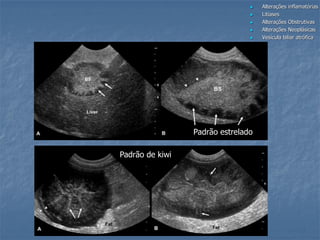

Colecistite aguda (Mucocele)

 colecistite enfizematosa = espessamento da

parede, artefatos de reverberação, sedimento

 mucocele da vesícula biliar = aguda, necrose da

parede (espessamento da parede com conteúdo

luminal imóvel de padrão radiado ou kiwi, pode

estar associada a obstrução biliar, perfuração

eminente

 colecistite necrotizante = irregularidade

acentuada, espessamento assimétrico da

parede, coleção fluida pericolecística (secundário

a ulceração, hemorragia ou necrose), variação

da mucocele

Padrão estrelado

Padrão de kiwi